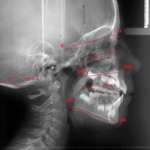

Le recentissime innovazioni tecnologiche applicate all’odontoiatria semplificano il flusso di lavoro e supportano con efficienza l'operato del clinico, consentendo di affrontare in sicurezza anche i casi ortodontici più complessi che vedono coinvolti pazienti pediatrici. La moderna Ortodonzia, che da qualche anno si avvale della tecnologia digitale, sta attraversando un periodo di massima espressione tecnologica, usufruendo delle ultime scoperte in campo informatico. A tal proposito anche l’Intelligenza Artificiale (IA) ha fatto il suo ingresso in campo ortodontico, supportando il clinico sia per quanto riguarda la diagnosi sia per quanto concerne la pianificazione del caso trattato.